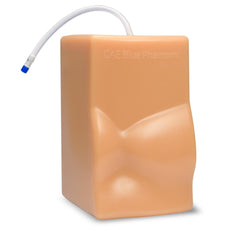

The model is of a supine adult male and extends from the upper buttocks to the lower neck. Positioned in the mid scapulary line, the ultrasound tissue insert contains chest wall superficial tissue, 6th, 7th, 8th, and 9th ribs and intercostal spaces, pleural cavity with lung and atelectatic lung, diaphragm, and superior spleen. The pleural fluid collections allow users to develop and refine their ultrasound guided thoracentesis skills. This model is extremely realistic and is self-healing offering you superb training with a low cost of ownership.

The ultrasound tissue insert offers extremely realistic sonographic imaging characteristics is designed for guiding the placement of needles and small catheters (18-21 gauge and associated catheter kits). Blue Phantom simulated human tissue is very realistic and ultra-durable; excellent for repeated training in skills associated with ultrasound guided thoracentesis procedures. Positive fluid flow offers users feedback when pleural effusions are accurately accessed. The fluid is easily refilled using a quick fill luer lock or can be connected to an I.V. reservoir for continuous fluid delivery. Users can also learn to avoid accessory structures as the spleen, diaphragm and lung.

Blue Phantom's mid-scapular thoracentesis ultrasound training model is specifically designed for ultrasound guided thoracentesis procedures. This ultrasound training phantom aids users in developing and practicing the skills associated with a mid scapulary approach to ultrasound guided thoracentesis procedures. This model is excellent for assisting clinicians in gaining proficiency in using ultrasound to identify and guide needle and small gauge catheter insertions in a patient with pleural effusions for diagnostic and/or therapeutic purposes.The model is of a supine adult male and extends from the upper buttocks to the lower neck. Positioned in the mid scapulary line, the ultrasound tissue insert contains chest wall superficial tissue, 6th, 7th, 8th, and 9th ribs and intercostal spaces, pleural cavity with lung and atelectatic lung, diaphragm, and superior spleen. The pleural fluid collections allow users to develop and refine their ultrasound guided thoracentesis skills. This model is extremely realistic and is self-healing offering you superb training with a low cost of ownership.

The ultrasound tissue insert offers extremely realistic sonographic imaging characteristics is designed for guiding the placement of needles and small catheters (18-21 gauge and associated catheter kits). Blue Phantom simulated human tissue is very realistic and ultra-durable; excellent for repeated training in skills associated with ultrasound guided thoracentesis procedures. Positive fluid flow offers users feedback when pleural effusions are accurately accessed. The fluid is easily refilled using a quick fill luer lock or can be connected to an I.V. reservoir for continuous fluid delivery. Users can also learn to avoid accessory structures as the spleen, diaphragm and lung.

- Mid-scapulary Thoracentesis Ultrasound Training Model

DIMENSIONS: Size: 17” long x 11” wide x 17” high (43 cm x 28 cm x 43 cm)

Weight: 20 lbs. (9 kg)